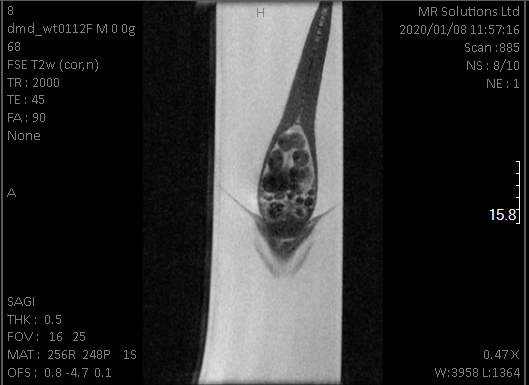

mri_fish

Killifish femal eggs